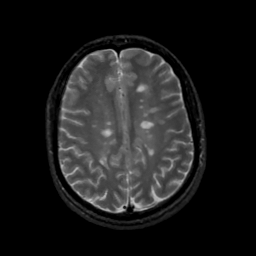

MR Study #13, May 19, 1991 -- Slice #34